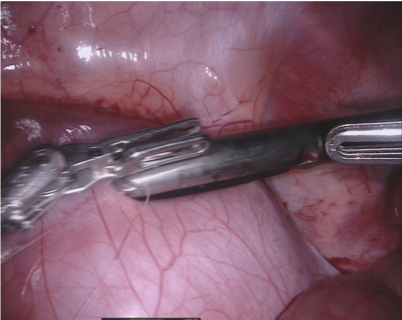

Our challenge was made up of 3 sub-problems. The first was binary instrument segmentation, where each frame was separated into da Vinci Xi instruments and a background class, which contained an ultrasound probe, surgical clips and porcine tissues. The second task was instrument part segmentation, where we scored the participants on whether they could correctly segment each articulating part of the instrument (see Fig. 3). Our final task was to segment and classify the instruments (see Fig. 4).

We provided the first 225 frames of 8 sequences as training data and kept the last 75 frames of those 8 sequences as test data. 2 of the full 300 frame sequences were kept as test sequences. Test labels were kept hidden from the participants. Our datasets contain 7 different robotic surgical instruments. The Large Needle Driver, Prograsp Forceps, Monopolar Curved Scissors, Cadiere Forceps, Bipolar Forceps, Vessel Sealer and additionally a drop-in ultrasound probe, which is typically held in the jaws of the Prograsp Forceps instrument. Samples from the training datasets are depicted in Fig. 2 and examples of the different instrument types are shown in Figure 3 and 4.

IV-D Type Segmentation

The final challenge was to identify each instrument type from the list of Large Needle Driver, Prograsp Forceps, Monopolar Curved Scissors, Vessel Sealer, Fenestrated Bipolar Forceps and Grasping Retractor (see Fig. 4). Only 6 teams participated in this challenge, due particularly to the significant increase in difficulty in recognizing many of the da Vinci instruments from one another.